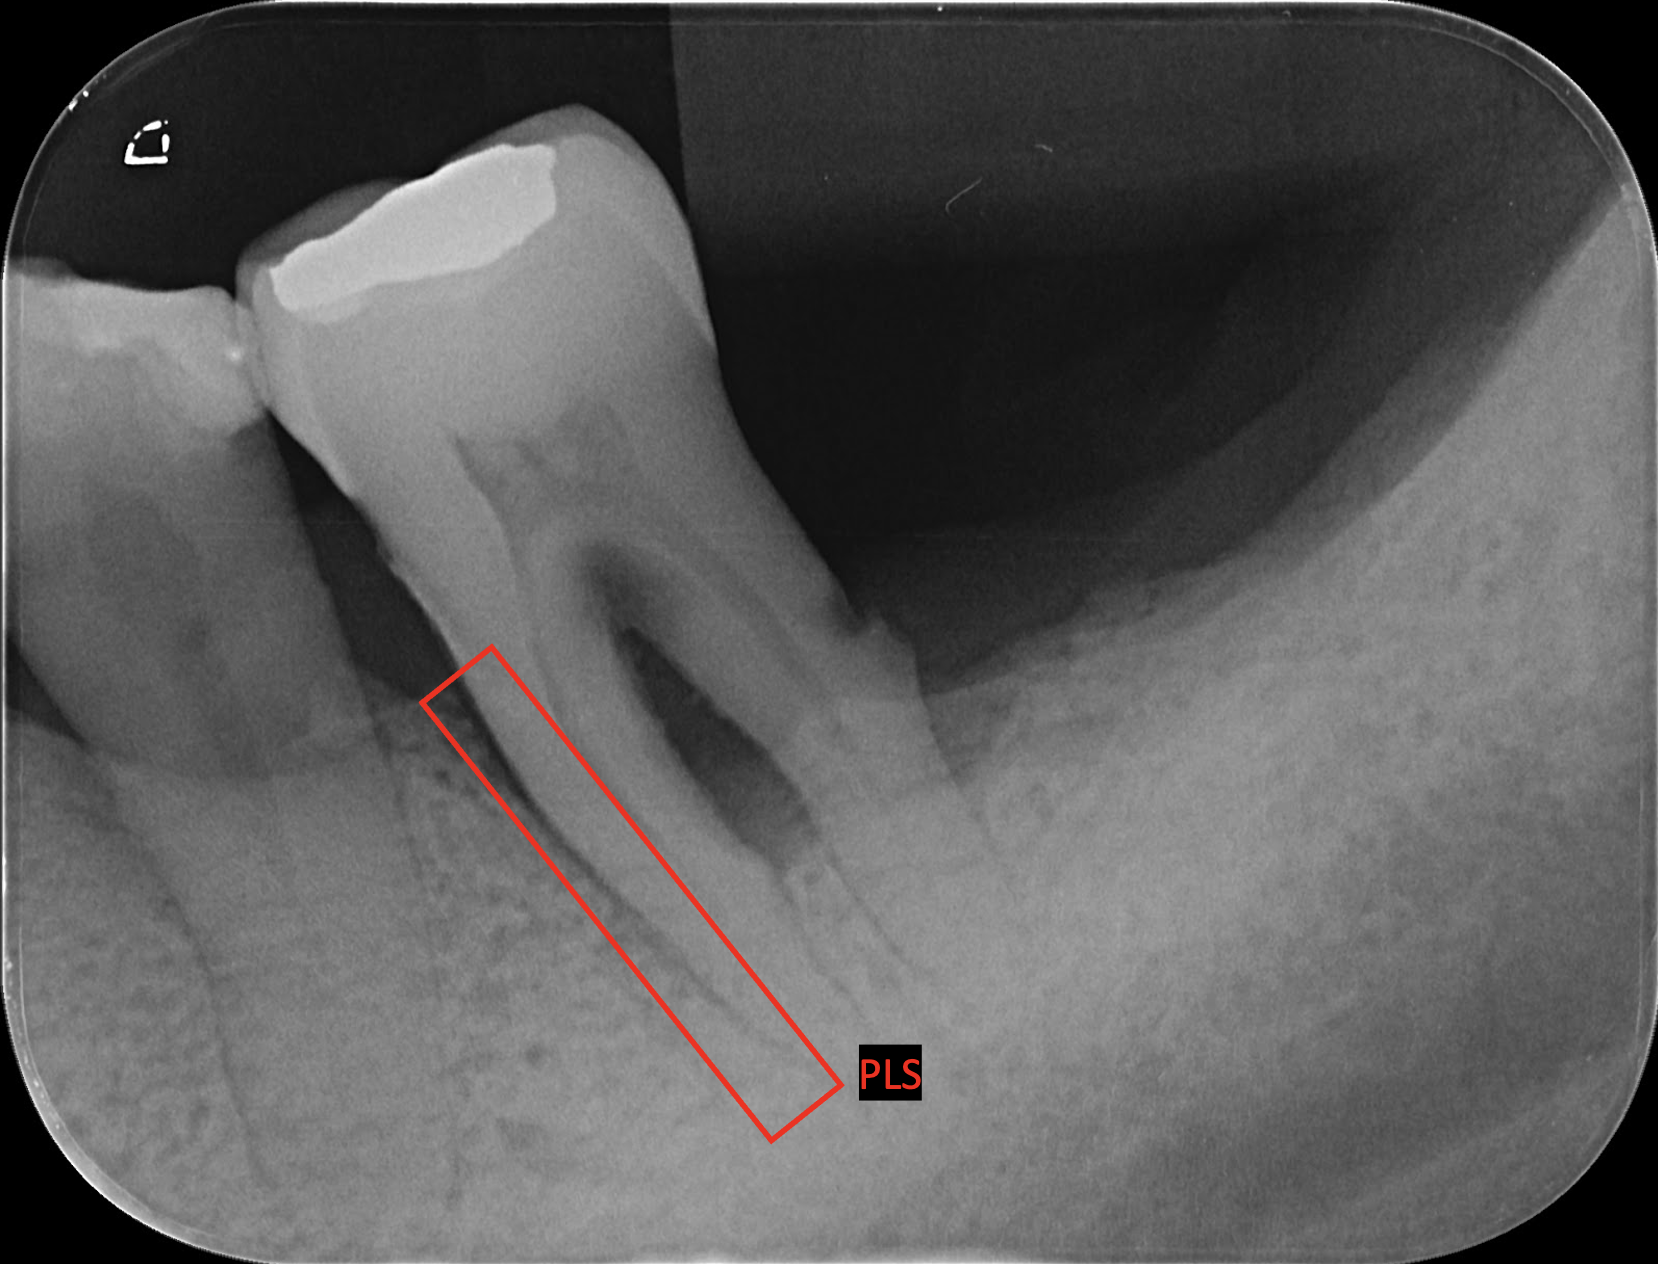

Periodontal Ligament Space (PLS)

In this step, areas where the periodontal ligament space had widened were annotated. PLS annotations in this category indicate ligament spaces that have widened from the tooth with a rotating bounding box, serving as indicators of compromised periodontal health rather than a healthy ligament space.

Given the limitations of some current pose estimation models, which do not support rotation indices for bounding boxes, we removed the rotational component from the TBB and PLS bounding boxes. We instead determine rotation using predicted segmentation from an auxiliary tooth segmentation model later on.